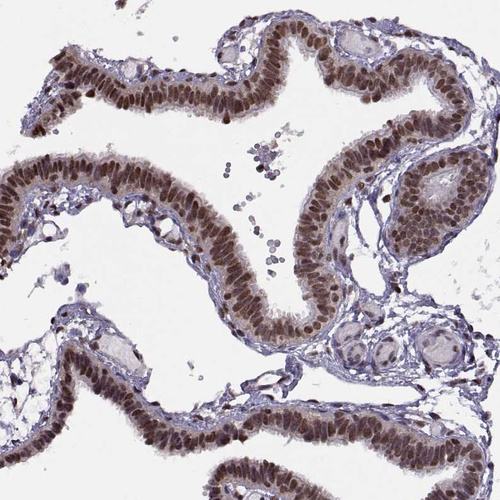

Immunohistochemical staining of human fallopian tube shows strong nuclear positivity in glandular cells.